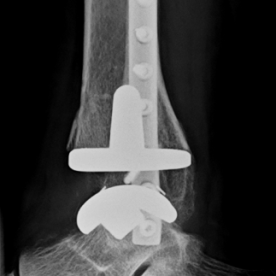

Bei einer Arthrose handelt es sich um eine Knorpelabnutzung in einem Gelenk, wobei unterschiedliche Ausprägungsgrade möglich sind. Je nach Ausprägungsart kommen konservative (Entzündungshemmende Medikamente, physikalische Therapie, orthopädische Hilfen) oder operative Verfahren (arthroskopische Spülung bzw. Gelenktoilette, Knochenumstellungen, Knorpelknochenzelltransplantationen oder prothetische Versorgung) in Frage.

Röntgenbilder